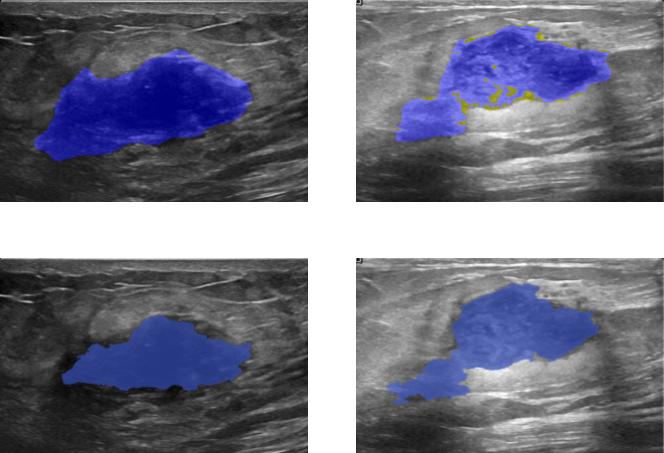

The figures below show the advantages and the limitation of our model in instance segmentation tasks. The Mask-RCNN[1] couldn’t capture the three dogs (top-left) and only segment two dogs as one and misclassify the remaining one as a horse while the three dogs are predicted appropriately but not well segmented due to occlusion inside the image. similarly for the top right prediction where the two men are well-segmented using our model. All in all, the Mask-RCNN[1] makes a lot of false alarms while our model predicts well the bounding boxes of objects. One limitation of our model is its lack of robustness to occlusion and hence it is not appropriate for predicting the mask of overlapping objects. Despite that, it is very efficient when it comes to segmenting the breast tumors since they are geologically not overlapping. The figures below shows two breast ultrasound scans with their corresponding predicted tumors (i.e, blue mask).

Benign tumors[43] share a number of features on ultrasound that indicate their benignity. In particular a round or oval shape , a large axis parallel to the skin, circumscribed margins or gently curving smooth lobulations , hyperechoic tissue in the case of solid tumors and anechoic content in the case of cysts and acoustic shadows in the edge. In contrast, malignant tumors[43] show specific features on ultrasound including, irregular shape with microlobulations or spiculations, a large axis that is not parallel to the skin, poorly defined margins, hypoechoic nodule or hetergenous echostructure and acoustic posterior shadowing. a visual analysis of the figures 4 and 5 prove that our model is able to capture the most relevant features we have already described.